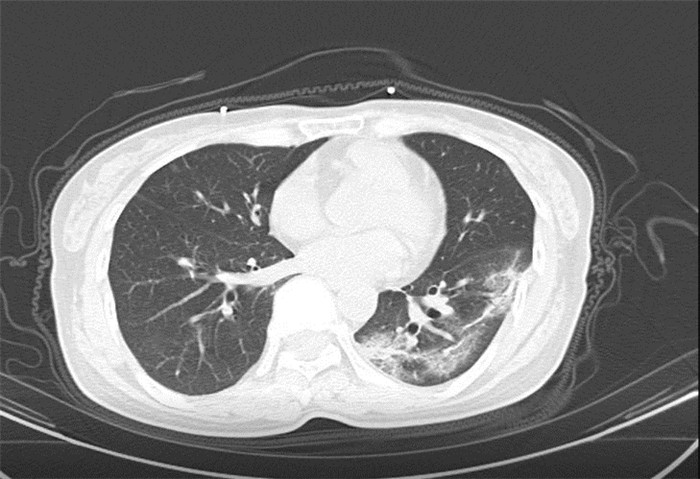

武漢大學(xué)中南醫(yī)院影像科副主任張笑春教授發(fā)現(xiàn),目前武漢市家庭聚集性發(fā)病較多,而且大多起病隱匿,一次甚至多次核酸陰性,無(wú)任何臨床癥狀,CT檢查卻已顯示為病毒性肺炎特征。

為了盡快篩查新型冠狀病毒肺炎患者,醫(yī)院會(huì)選擇影像診斷作為早期發(fā)現(xiàn)新型冠狀病毒感染的肺炎的重要一環(huán)。

CT為當(dāng)前首選篩查與診斷的主要影像學(xué)手段,胸部CT的病毒性肺炎檢出率高。

方舟CT(CT Ark)可以滿(mǎn)足全面的臨床功能,配置16層、32層、64層、128層CT,實(shí)現(xiàn)了低劑量掃描要求,配合NDI微劑量迭代技術(shù),智能毫安調(diào)控技術(shù),使各種場(chǎng)合下、各部位低劑量掃描得以實(shí)現(xiàn);超高分辨率CT病灶靶掃描,使病灶的密度顯示更加精確,能夠顯示病灶內(nèi)輕度的密度變化,有利于小病灶的密度定量分析和及時(shí)診斷。